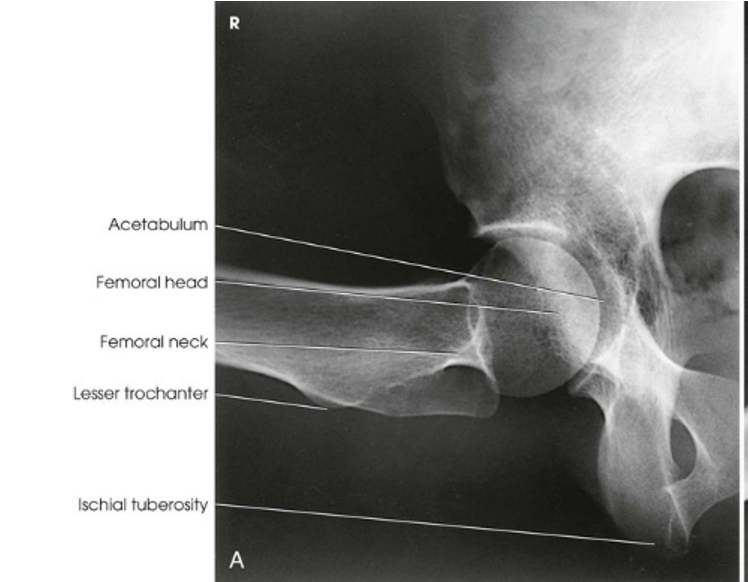

The bilateral image shows an AP oblique projection of the femoral heads, necks, and trochanteric areas onto one radiograph for comparison

AP Oblique Projection; Proximal Femora and Femoral Necks; Modified Cleaves Method